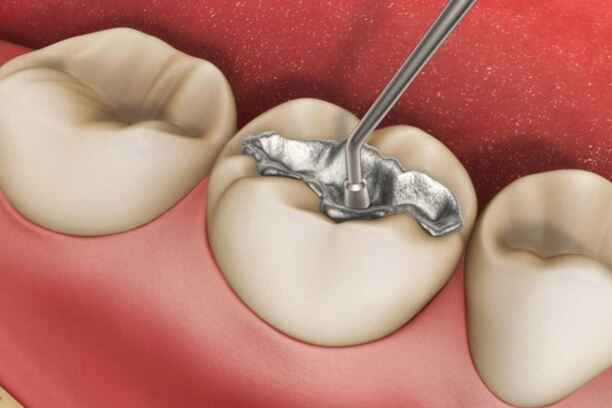

2- الحشو المعدني

الحشو المعدني، المعروف بحشو الأملغم، يُستخدم منذ عقود طويلة ولا يزال خيارًا فعالًا في بعض الحالات، خاصة في الأسنان الخلفية التي تتحمل ضغط المضغ العالي. ويُعد أقل الخيارات تكلفة عند الحديث عن سعر حشو اسنان.

☆ مميزات الحشو المعدني

- قوة تحمل عالية وقدرة ممتازة على مقاومة الضغط والمضغ.

- عمر افتراضي طويل قد يتجاوز 10 سنوات في بعض الحالات.

- تكلفة منخفضة مقارنة ببقية أنواع الحشوات.

- سرعة التركيب وعدم الحاجة إلى تقنيات معقدة.

☆ عيوب الحشو المعدني

- لون داكن غير جمالي، يجعله غير مناسب للأسنان الأمامية.

- قد يتطلب إزالة جزء أكبر من السن السليم لتثبيته.

- يحتوي على الزئبق بنسبة ضئيلة، ما يثير مخاوف لدى بعض المرضى.

- قابلية حدوث تمدد وانكماش مع تغير درجات الحرارة.